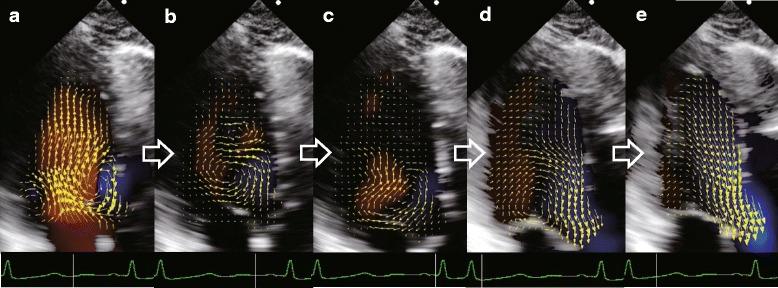

Vector flow mapping analysis of left ventricular energetic performance in healthy adult volunteers.

Vector flow mapping, a novel flow visualization echocardiographic technology, is increasing in popularity. Energy loss reference values for children have been established using vector flow mapping, but those for adults have not yet been provided. We aimed to establish reference values in healthy adults for energy loss, kinetic energy in the left ventricular outflow tract, and the energetic performance index (defined as the ratio of kinetic energy to energy loss over one cardiac cycle).

Transthoracic echocardiography was performed in fifty healthy volunteers, and the stored images were analyzed to calculate energy loss, kinetic energy, and energetic performance index and obtain ranges of reference values for these.